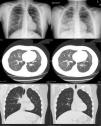

Caso 1.Paciente de 3 años. A los 21 meses presentó una bronquiolitis por VRS, que necesitó hospitalización, y después numerosas bronquitis sibilantes, una de ellas con neumonía en el lóbulo inferior derecho. Aportaba radiografías de tórax previas normales. La exploración inicial y el estudio de inmunodeficiencias, FQ y neumopatías resultaron normales. A los pocos meses, se objetivó una hipoventilación en el hemitórax izquierdo, inadvertida previamente. Una radiografía de tórax demostró engrosamiento broncovascular en el lóbulo medio e hiperclaridad en el hemitórax izquierdo. La TAC torácica mostró hallazgos compatibles con síndrome de Swyer-James-MacLeod (fig. 1). Cuando el niño pudo colaborar, las radiografías de tórax en inspiración/espiración mostraron un pulmón izquierdo reducido en inspiración y con atrapamiento aéreo en espiración.

Arriba: radiografías de tórax en inspiración y espiración, mostrando un pulmón izquierdo menor, que atrapa aire en espiración. Medio y abajo: TAC torácica. Se observan áreas parcheadas de hiperaireación, menos evidentes en el hemitórax derecho. Pulmón izquierdo con hiperaireación prácticamente en su totalidad, con excepción de la língula, bronquiectasias cilíndricas en toda la pirámide basal y disminución de volumen del LI y, por lo tanto, del hemitórax.